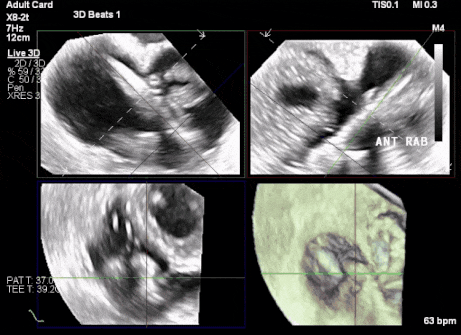

術(shù)前超聲顯示三尖瓣重度反流合并拴系

術(shù)中TEE成像困難,偽影干擾

術(shù)后DSA、超聲顯示人工瓣膜穩(wěn)定性良好,瓣葉啟閉正常,無瓣周漏